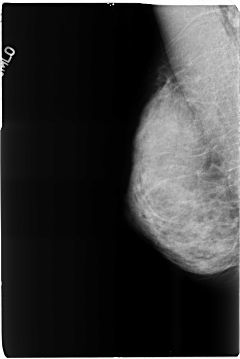

B_3516_1.RIGHT_CC

RIGHT_CC LINES 4680 PIXELS_PER_LINE 3104 BITS_PER_PIXEL 12 RESOLUTION 50 NON_OVERLAY

RIGHT_MLO LINES 4664 PIXELS_PER_LINE 3112 BITS_PER_PIXEL 12 RESOLUTION 50 NON_OVERLAY